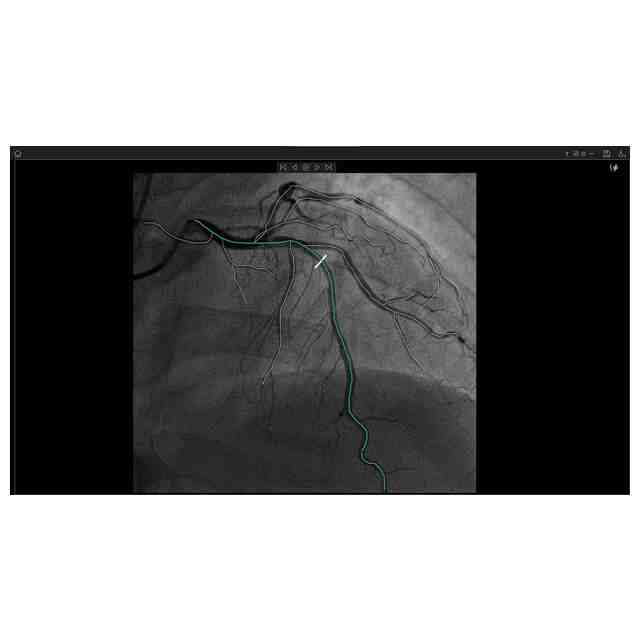

画像図及び変化後を示す画像図1~3は、例えば、複数の医療用画像を登録した後に表示して分析するために用いられる。使用状態を示す参考図1~6、変化後を示す画像図1の使用状態を示す参考図1~5、変化後を示す画像図2の使用状態を示す参考図、及び、変化後を示す画像図3の使用状態を示す参考図は、医療用画像データを分析するに際し、表示される図を示したものである。変化後を示す画像図1は、画像図における下方において黄色で示されたウインドウの右上隅にある「非表示」ボタンが押されると表示される画像である。変化後を示す画像図2は、変化後を示す画像図1における黄色で示された左端のウインドウがダブルクリックされると表示される画像であり、変化後を示す画像図2における黄色で示されたウインドウがダブルクリックされると画像図に戻る。変化後を示す画像図3は、画像図における黄色で示された中央のウインドウがダブルクリックされると表示される画像である。

図面中、黄色で示された部分以外の部分が部分意匠として意匠登録を受けようとする部分である。